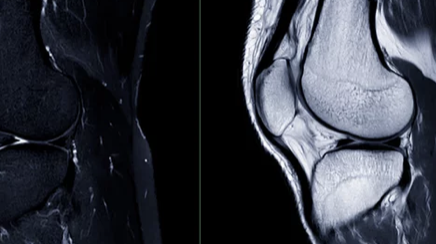

무릎 연골 손상을 의심한다면 전문의 진료를 받아 정확한 진단을 받는 것이 중요합니다. 진단에는 다음과 같은 방법들이 사용됩니다.

- X-ray: 뼈 손상 여부를 확인

- MRI: 연골 상태를 정확하게 진단

- CT: 뼈와 연골 상태를 자세하게 확인